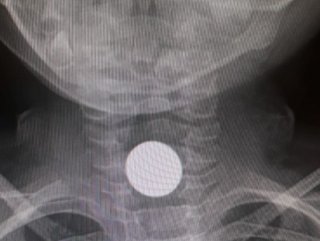

Ailesi, aniden fenalaşan çocuğu hastaneye kaldırdı. Burada çekilen röntgende küçük çocuğun boğazına metal para kaçtığı anlaşıldı.